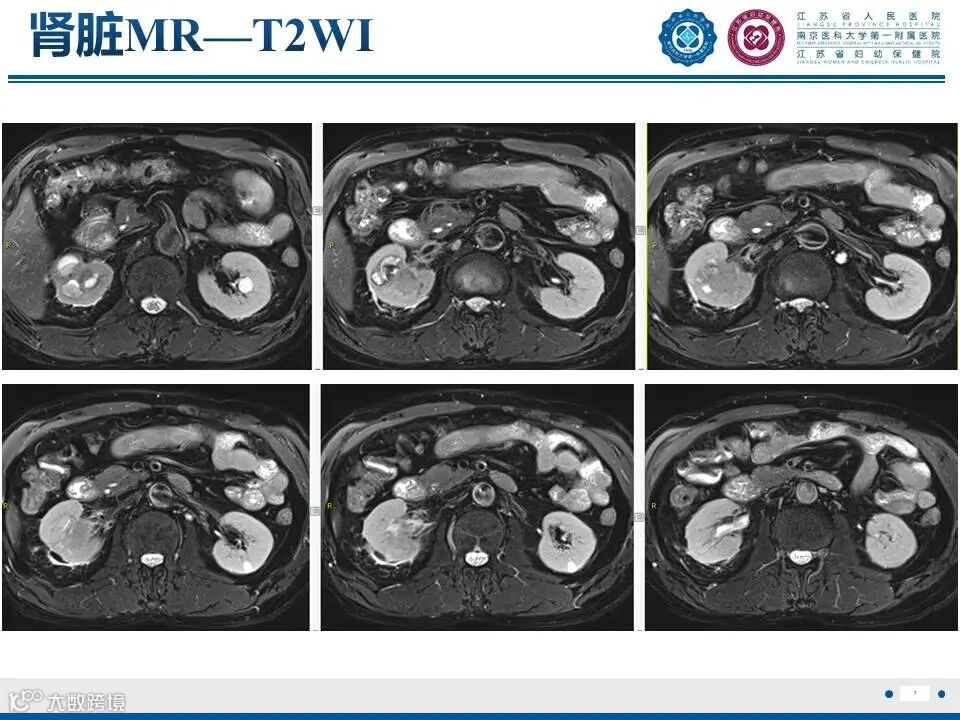

肾实质肾盂尿路上皮癌——水泄不通 II

肾实质肾盂尿路上皮癌——水泄不通 II 鼎湖影像